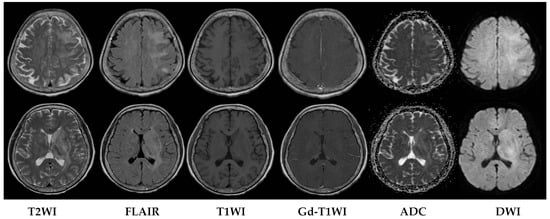

Upon evaluation, her fever persisted at 38.2 degrees Celsius, and laboratory investigations revealed leukopenia with a white blood cell count (WBC) of 610/μL. The urinalysis showed no evidence of pyuria, and the chest X-ray results were unremarkable. The treatment included the administration of Granulocyte Colony-Stimulating Factor (GCSF) for leukopenia and empirical antibiotics, specifically piperacillin/tazobactam, to address the neutropenic fever. An extensive infectious workup was conducted on admission, including a cerebrospinal fluid (CSF) analysis, which did not identify a clear infectious focus. The blood cultures yielded no bacterial growth. The patient’s WBC count elevated to 7430/μL after GCSF treatment. However, intermittent fever was still observed. Six days after admission, she exhibited a slow response and developed right-sided weakness. A relapse of CNS lymphoma or other CNS lesion was suspected. A brain computed tomography (CT) scan revealed abnormal hypointense changes in the left frontal lobe, left basal ganglion, left thalamus, and left cerebral peduncle with associated brain swelling (Figure 1). The subsequent magnetic resonance imaging (MRI), performed three days later, revealed hyperintensity in the left frontal and left parietal lobes, bilateral corona radiata, basal ganglia, and thalami, as well as the left temporal lobe and left-side brainstem on T2 weighted images (T2WIs), fluid attenuated inversion recovery (FLAIR), and diffusion weighted images (DWIs) without obvious restricted diffusion. No definite contrast enhancement was observed on the post-gadolinium T1 weighted images (Gd-T1WIs) (Figure 2). The presence of a mass effect from the infiltrative lesions, resulting in the compression of the left lateral ventricle and a midline shift to the right side, was observed. Notably, magnetic resonance spectroscopy (MRS) focused on the left basal ganglion lesion showed an elevated choline peak and decreased N-acetylaspartate (NAA) peak, with the presence of a lactate peak (Figure 3). A stereotactic brain biopsy for the left basal ganglion lesion and the left frontal lobe lesion confirmed the presence of diffuse large B-cell lymphoma, and the patient subsequently received whole-brain radiotherapy. Following treatment, the patient’s consciousness improved to an alert state (E4V5M6), and her right limb muscle strength showed improvement. Under stable conditions, she underwent another cycle of R-CHOP chemotherapy and completed whole-brain radiotherapy (WBRT). The patient was transferred to a nursing home under a stable clinical condition.

Figure 2. MRI performed three days after CT scan. MRI fused images of axial T2WI, FLAIR, T1WI, Gd-T1WI, ADC, and DWI images. Abnormal hyperintense lesions are seen at left frontal lobe, left parietal lobe, bilateral corona radiata, bilateral basal ganglia, bilateral thalami on FLAIR, DWI, and ADC images. No obvious contrast enhancement or restricted diffusion is seen.